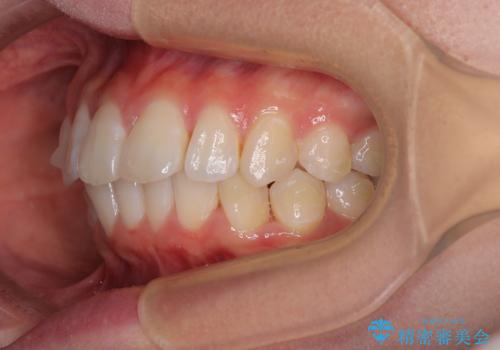

深い咬み合わせによる隙間 インビザライン矯正でコンプレックスを改善

- 上の前歯の隙間を気にして来院された患者様です。

インビザラインにより、上下の歯列を側方に拡大しつつ、前歯の隙間を閉じていくこととしました。

隙間の原因は強い咬合力や舌の突出癖、小帯の異常付着などがありますが、舌のトレーニングをしっかりと行いながら、装着時間を遵守して装着していただいたおかげで、スムーズに治療を終えることができました。